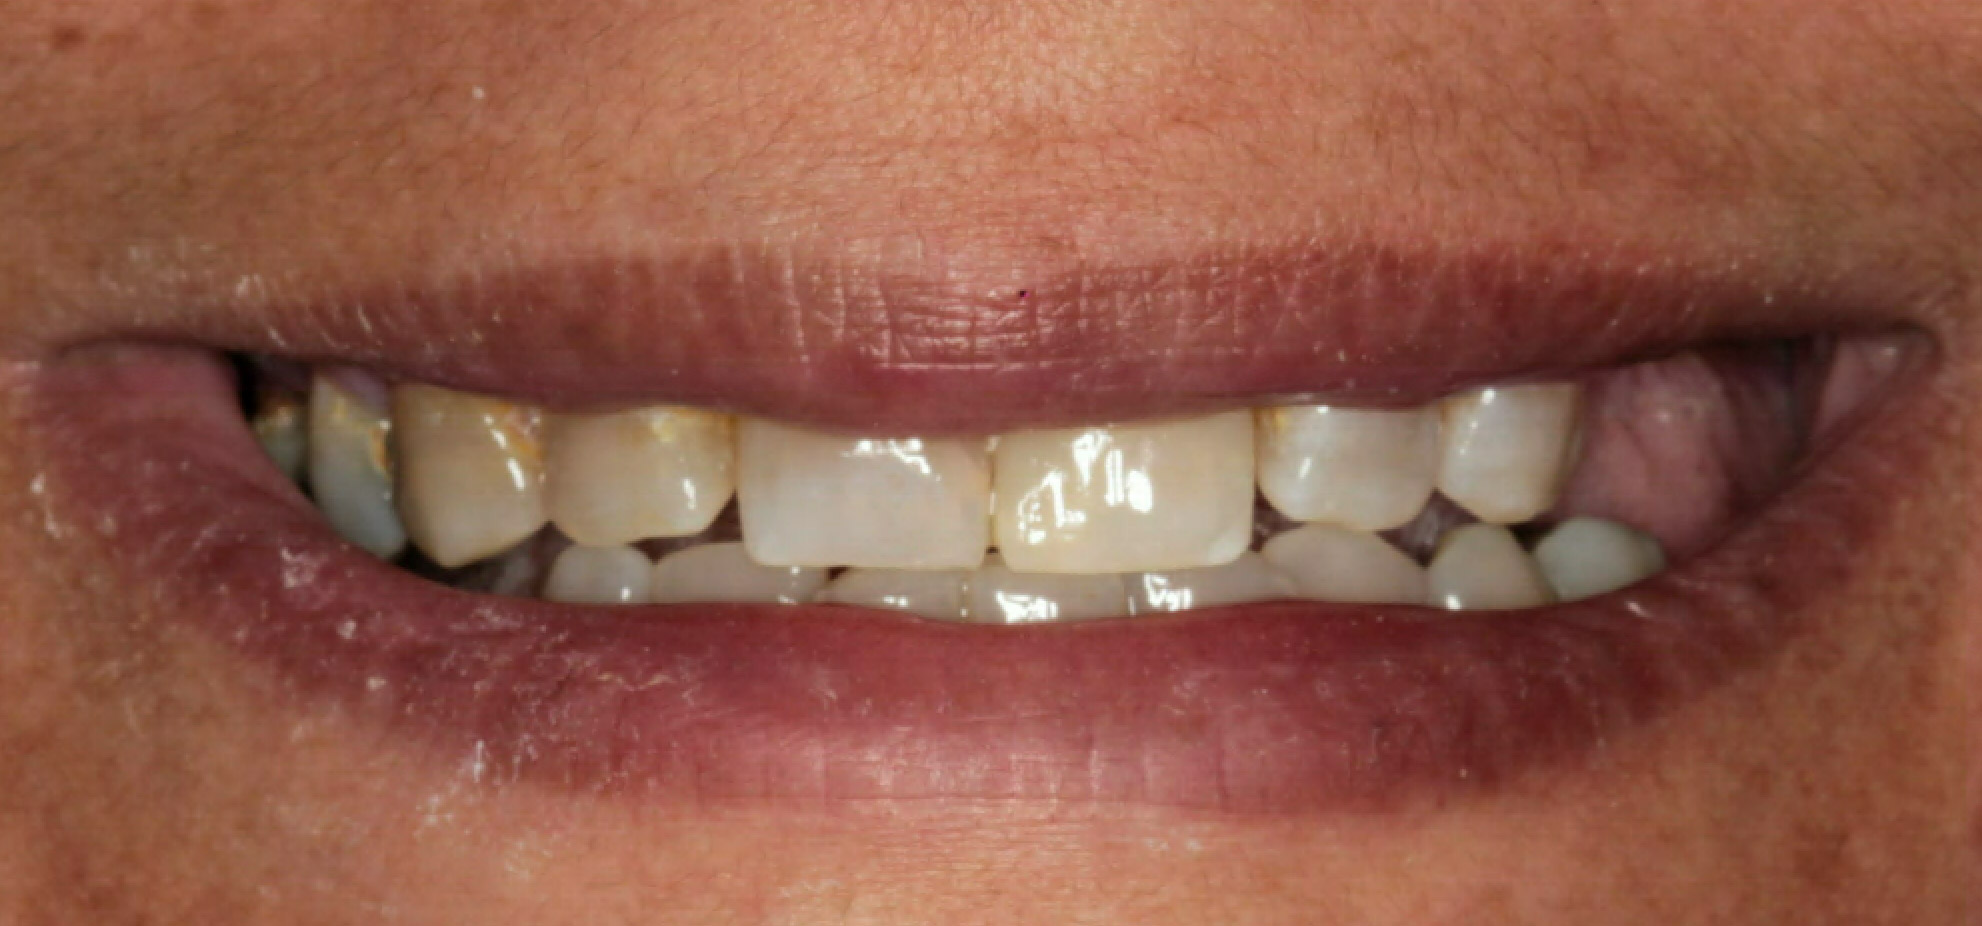

VII. INTRA ORAL PICTURES

Intra Oral Pictures (1)

(Treatment in progress)

Intra Oral Pictures (2)